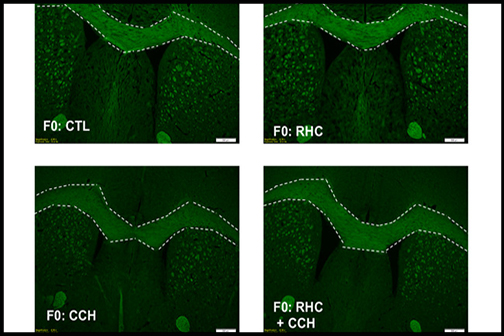

Study Suggests Epigenetic Treatment May Prevent Memory Loss in Vascular Dementia

An LSU Health New Orleans research team working in a mouse model of vascular cognitive impairment (VCI) has found that repetitive exposure to environmental hypoxia (air with lower-than-normal oxygen content) prevented memory loss. They also demonstrated for the first time that offspring can inherit this protection against dementia. More